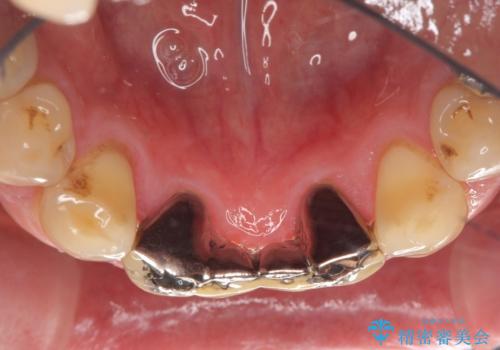

かみ合わせもきつく、ジルコニアクラウンではセラミックでも欠けてしまいそうでした。

今回は、丈夫な欠けにくいフルジルコニア(ヴェレッツァ)クラウンでブリッジにすることにしました。

- 32万円(下顎2−2:フルジルコニアクラウン(ヴェレッツァクラウン・スタンダード)7万円x4本、仮歯1万円x4本)費用は治療当時の料金となります

ジルコニアクラウンの方が再現性は優れていますが、ヴェレッツァでも多少色合いなど相談に乗ります。